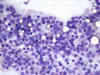

ID the cells

Lymphoblasts